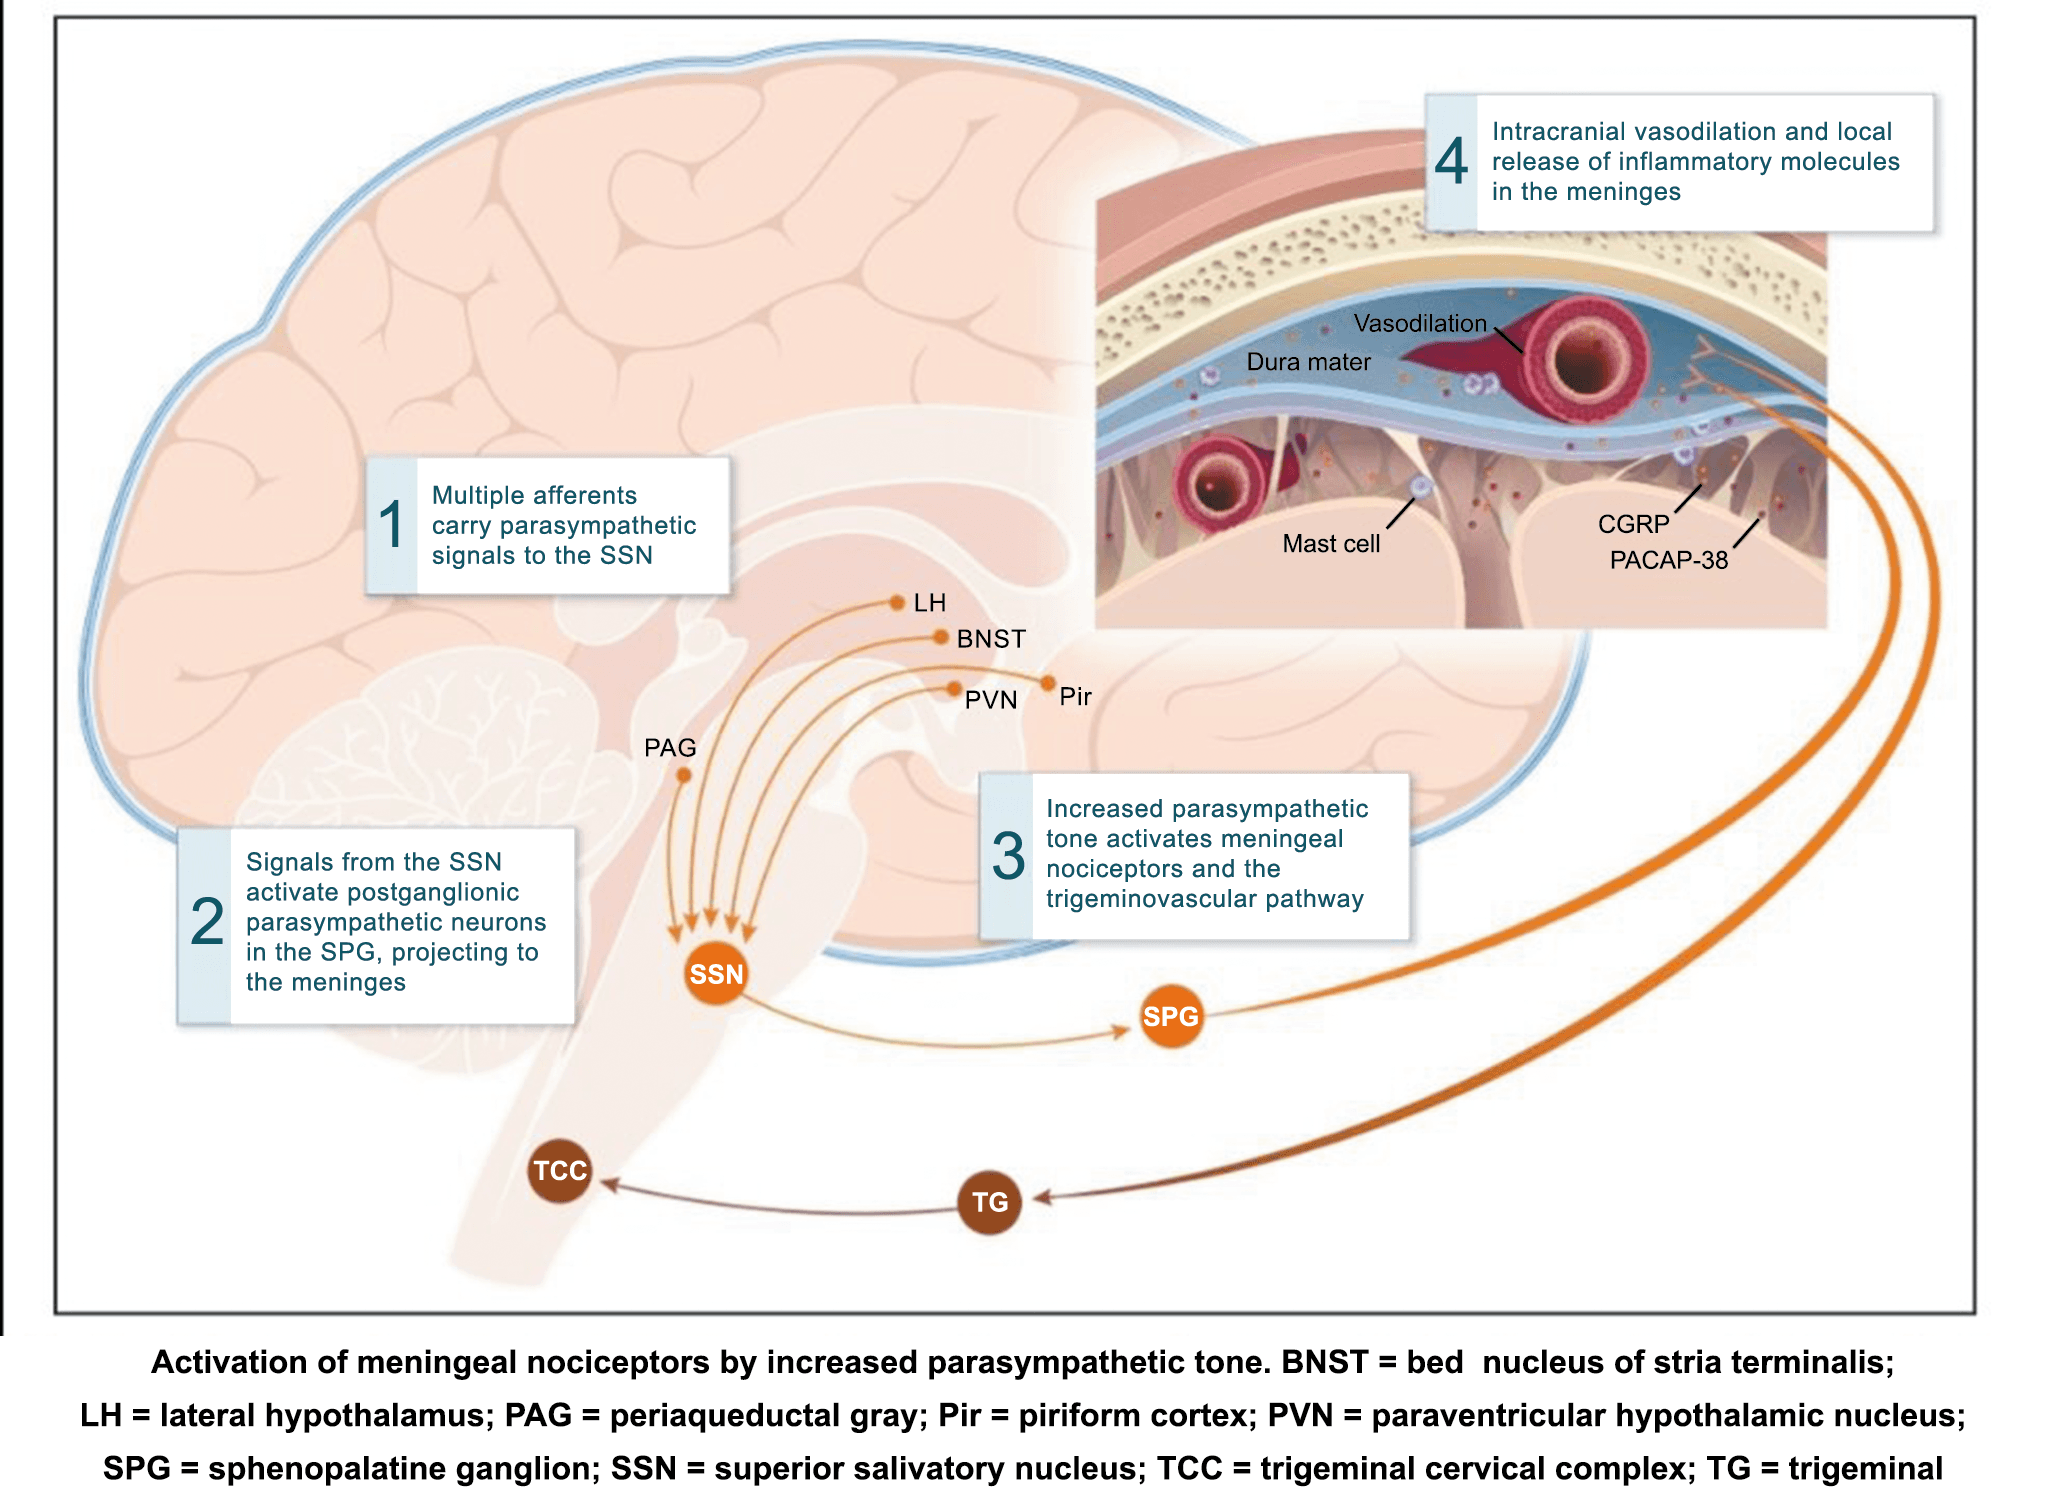

La importancia de la vasculatura intracraneal, o su inervación de fibras nerviosas, sigue siendo significativa. Los estudios de Ray y Wolff(94) demostraron que la estimulación de la duramadre, particularmente alrededor de los vasos sanguíneos durales y cerebrales, puede generar dolor similar al de la cefalea, además de náuseas, mientras que la estimulación lejos de los vasos fue ineficaz. Como se describió anteriormente, los vasos sanguíneos de la duramadre están ricamente inervados por axones nociceptivos no mielinizados (fibras C) y mielinizados (fibras Aδ) que se originan en el ganglio del trigémino y contienen neuropéptidos vasoactivos (serotonina, dopamina, histamina, péptido relacionado con el gel de la calcitonina). Estos datos consolidan la teoría de que la cefalea en la migraña está mediada por la activación de las fibras nerviosas nociceptivas que inervan los vasos sanguíneos meníngeos. La pregunta clave es qué hace que estas fibras se activen durante la migraña. Una propuesta en la década de 1980 fue que una “inflamación neurogénica estéril” de las meninges durales puede resultar en la activación de la inervación perivascular para desencadenar la migraña(95). La activación está impulsada por la liberación dural local de mediadores inflamatorios endógenos como CGRP, sustancia P, neuroquinina A y prostaglandinas, que aumentan el flujo sanguíneo local (predominantemente impulsado por CGRP), la fuga de proteínas plasmáticas de los vasos sanguíneos, la desgranulación de mastocitos y la agregación de las plaquetas.

Un principio importante de esta teoría es que el desencadenante principal de la migraña proviene de la periferia, en los vasos sanguíneos de la duramadre, con la activación del sistema trigeminovascular proveniente del disparo de las neuronas trigeminales periféricas de primer orden en respuesta a una lesión nociceptiva o señales provenientes de las meninges que liberan mediadores neuroinflamatorios. La activación sostenida de las neuronas nociceptivas meníngeas durales provoca la activación secuencial y la sensibilización de las neuronas trigeminovasculares de primer orden (nociceptores periféricos), segundo orden (a nivel del TCC-complejo trigémino cervical) y tercer orden (trigeminotalámico), (Figura 5) así como la activación ascendente del cerebro, tallo y otras estructuras diencefálicas(97).

Los terminales axónicos de las fibras nerviosas nociceptivas que inervan la duramadre contienen neuropéptidos vasoactivos CGRP, sustancia P, neurocinina A y péptido activador de la adenilato ciclasa pituitaria (PACAP)(25) (Figuras 13 y 14), que se cree que son liberados tras la estimulación que causa la vasodilatación de los vasos durales y piales(26) (Figura 15).

La activación del sistema trigeminovascular da como resultado la liberación de varios neuropéptidos basados en las inervaciones simpática, parasimpática y sensorial de la vasculatura craneal, que se resumen en la figura 23.

La inervación simpática se caracteriza por NPY y norepinefrina(52), ambos de los cuales son vasoconstrictores, mientras que las fibras parasimpáticas se caracterizan por VIP y PACAP, que se encuentran entre los vasodilatadores más potentes(24).

Las inervaciones sensoriales se caracterizan por la sustancia P, CGRP y PACAP (53).